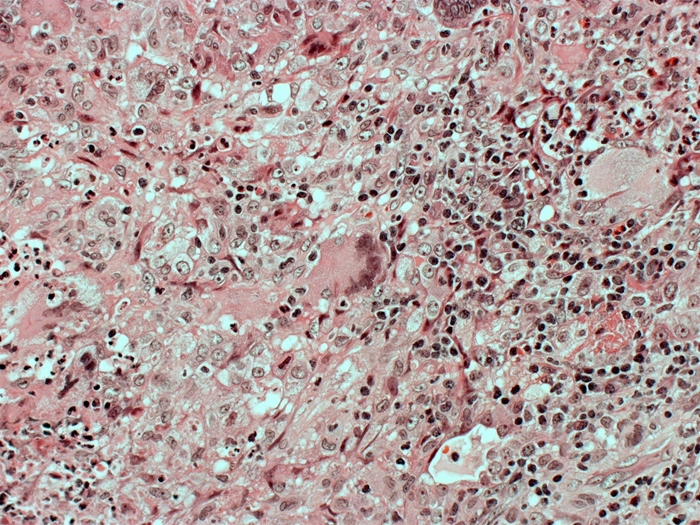

A 64-year-old man visits the clinic after experiencing many weeks of continuous coughing, fever, and weight loss. He smokes a pack of cigarettes every day and consumes 10 to 12 beers on weekends. An infiltration in the left upper lobe is shown by a chest x-ray. Despite receiving broad-spectrum antibiotic therapy for both aspiration and community-acquired pneumonia, the patient's symptoms deteriorate. The Gram stain on sputum does not indicate any microbes. The following picture depicts the results of a lung biopsy:

Which of the following substances is most important for driving the development of this patient's observed microscopic lesion?

F)Interferon-gamma

Which of the following substances is most important for driving the development of this patient's observed microscopic lesion?A)C3a